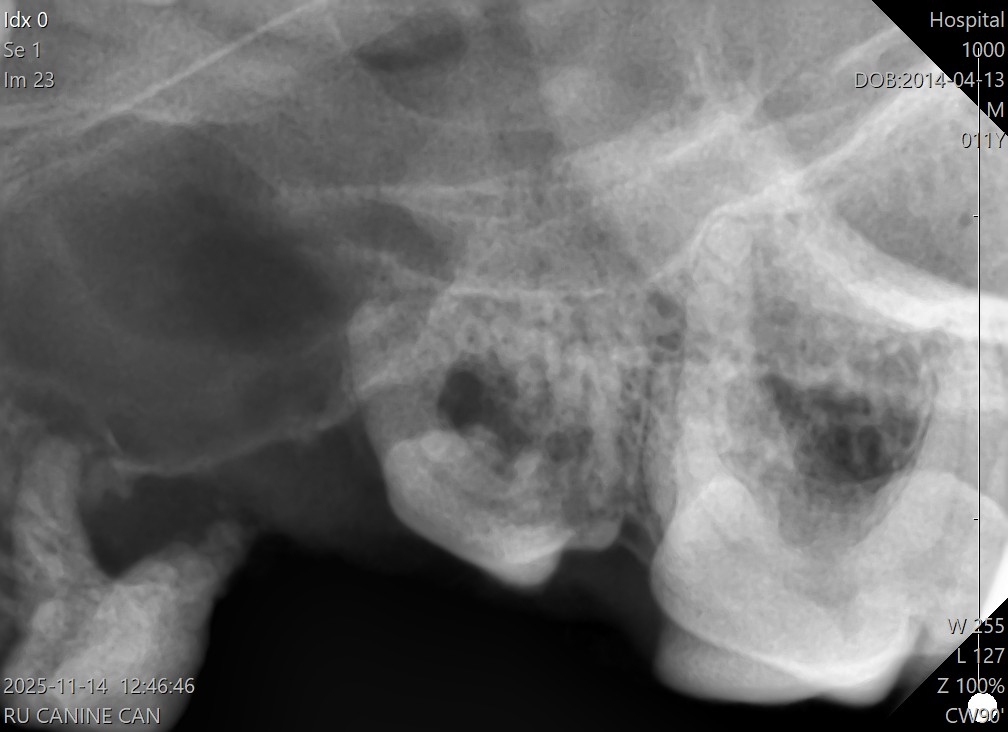

歯周ポケットの確認や歯科レントゲン撮影は、口腔内にブローブを入れるため 基本的には術直前に全身麻酔下で行います。

Lちゃんの場合歯周病の進行が著しく、既にぐらつきがあるもの 外見ではわからなかった歯根の周りの顎の骨が溶けている部分もレントゲンで確認できました。